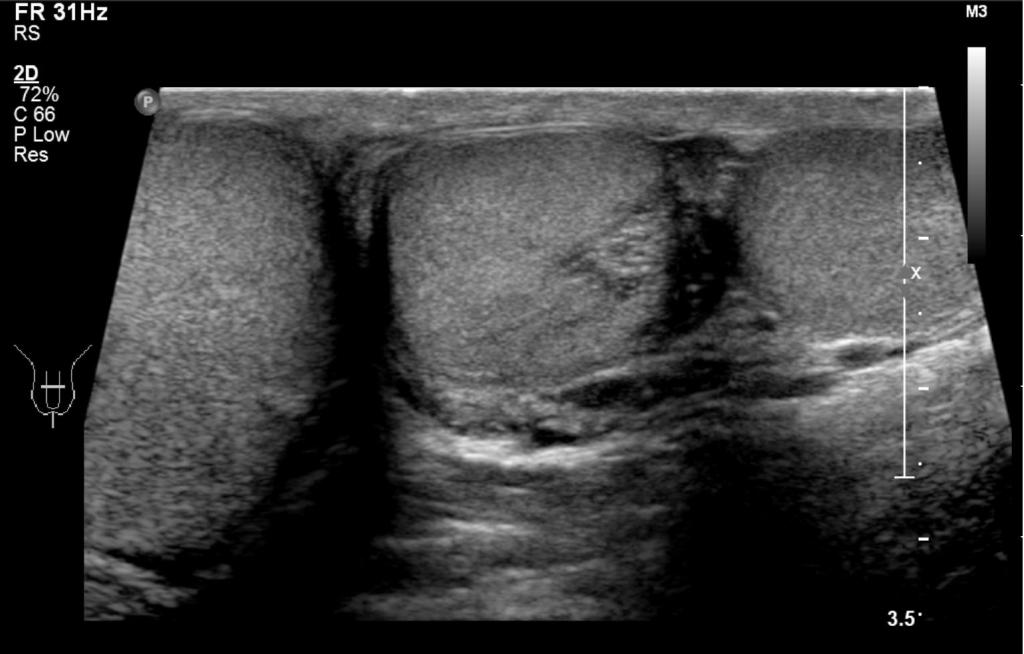

Een 32-jarige man werd naar de polikliniek Urologie verwezen vanwege een zwelling in het linker hemiscrotum. De zwelling was sinds de jeugd aanwezig, constant van omvang en niet drukpijnlijk. Patiënt had 2 kinderen. Lichamelijk onderzoek toonde links in het scrotum 2 ovaalvormige, gladde, vast-elastische zwellingen. Bij palpatie was er 1 ductus deferens voelbaar. Rechtszijdig was een niet-afwijkende testis aanwezig. Er werd echografisch onderzoek gedaan (klik op de afbeelding voor volledige weergave).